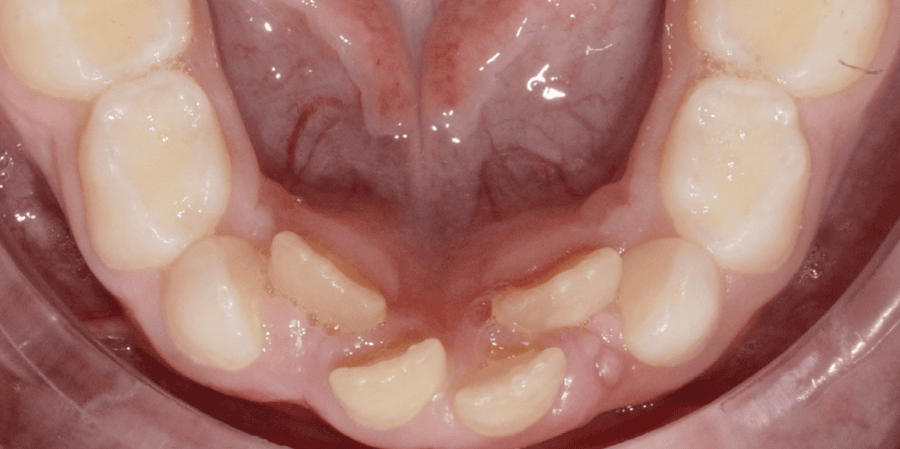

Before